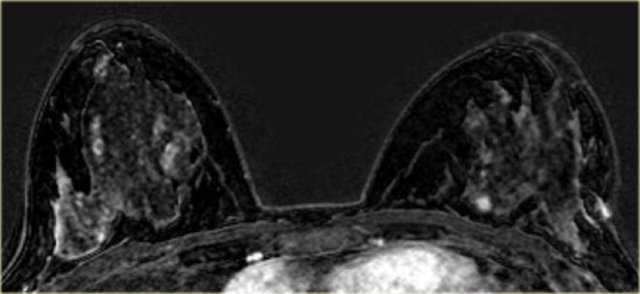

On the left a patient with areas of non-mass enhancement in both breasts (DCIS).

There is a small enhancing mass medially in the left breast, which was a small invasive carcinoma.

On the left another case with diffuse, bilateral DCIS.

Another case of DCIS, located laterally in both breasts.